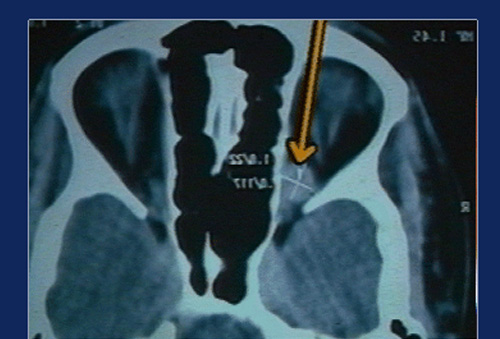

Transnasal Endoscopic approach is employed for removal of tumours and other lesions from the medial and infero medial orbit. The lamina papyracea is a paper thin bone, which can be deliberately opened to expose the orbital contents and extraconal lesions can be removed without much difficulty.

The medial rectus fills almost the entire medial orbit and prevents exposure of the intraconal structures and orbital apex. We have devised a technique of retracting this muscle downwards and posteriorly without compromising its function to obtain good exposure of the Orbital Apex. Well defined, capsulated lesions can be successfully and completely removed using this technique, with little morbidity. We have employed this technique in 30 cases and almost perfected it.

An endoscopic medial orbitotomy and medial retraction techniques were employed to expose the tumour and the same removed in toto